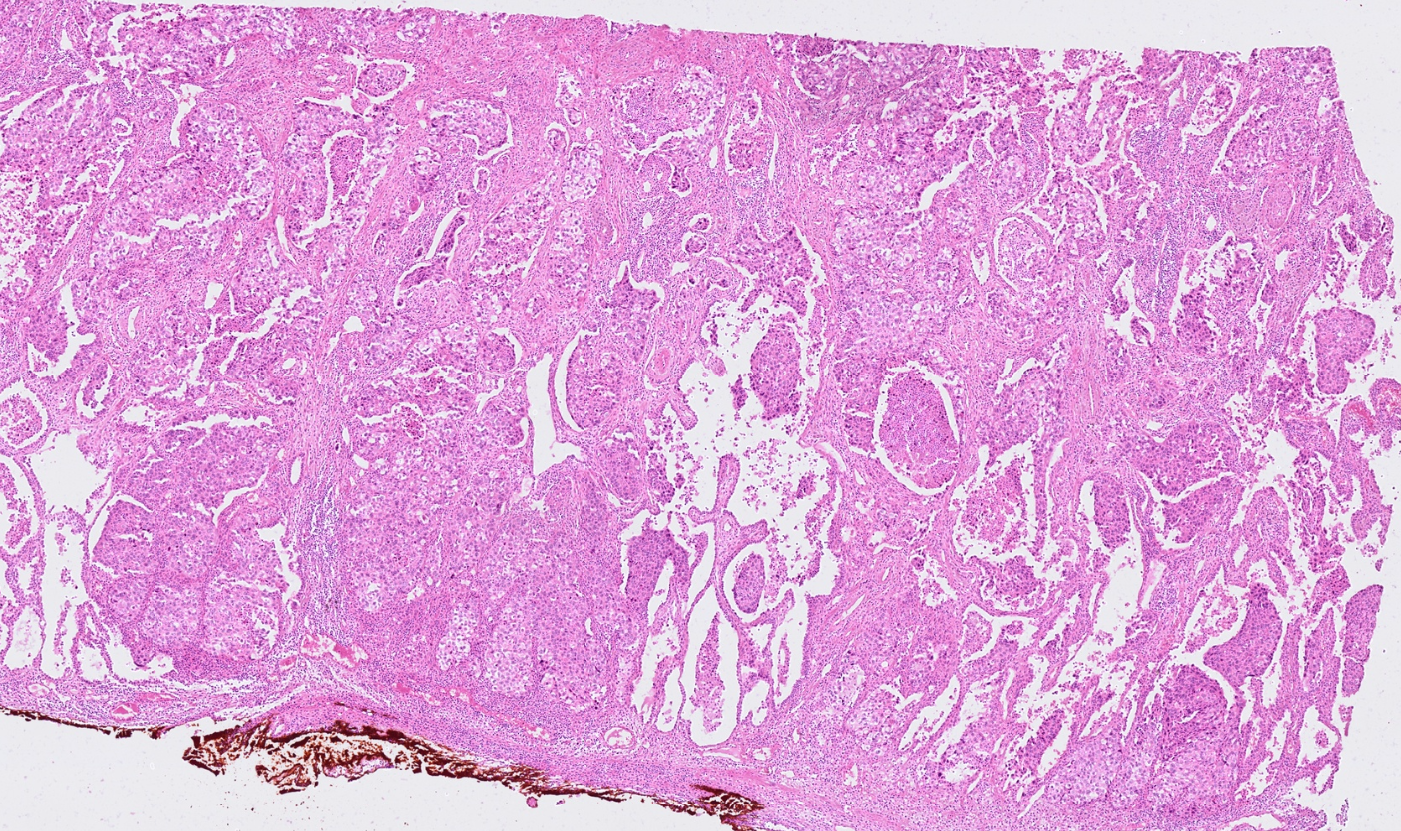

The segmentation module is designed to generalize across a wide range of biological tissues. Below are representative benchmark results based on 10x Genomics demo datasets:

Brain

Pancreas

Colon

Liver

Ovary

Kidney

Lung

Skin

Lymph node